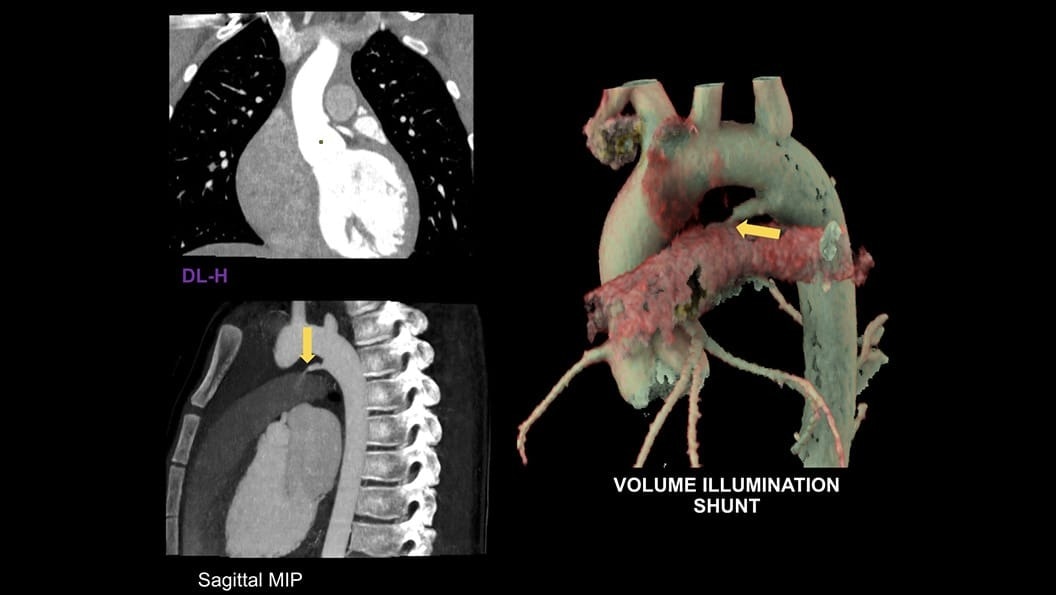

CT-Guided Interventional Care

Since becoming an important step in the patient care pathway and heart care guidelines, CT images are an invaluable tool in the cath lab, guiding procedures for precise personalized care.